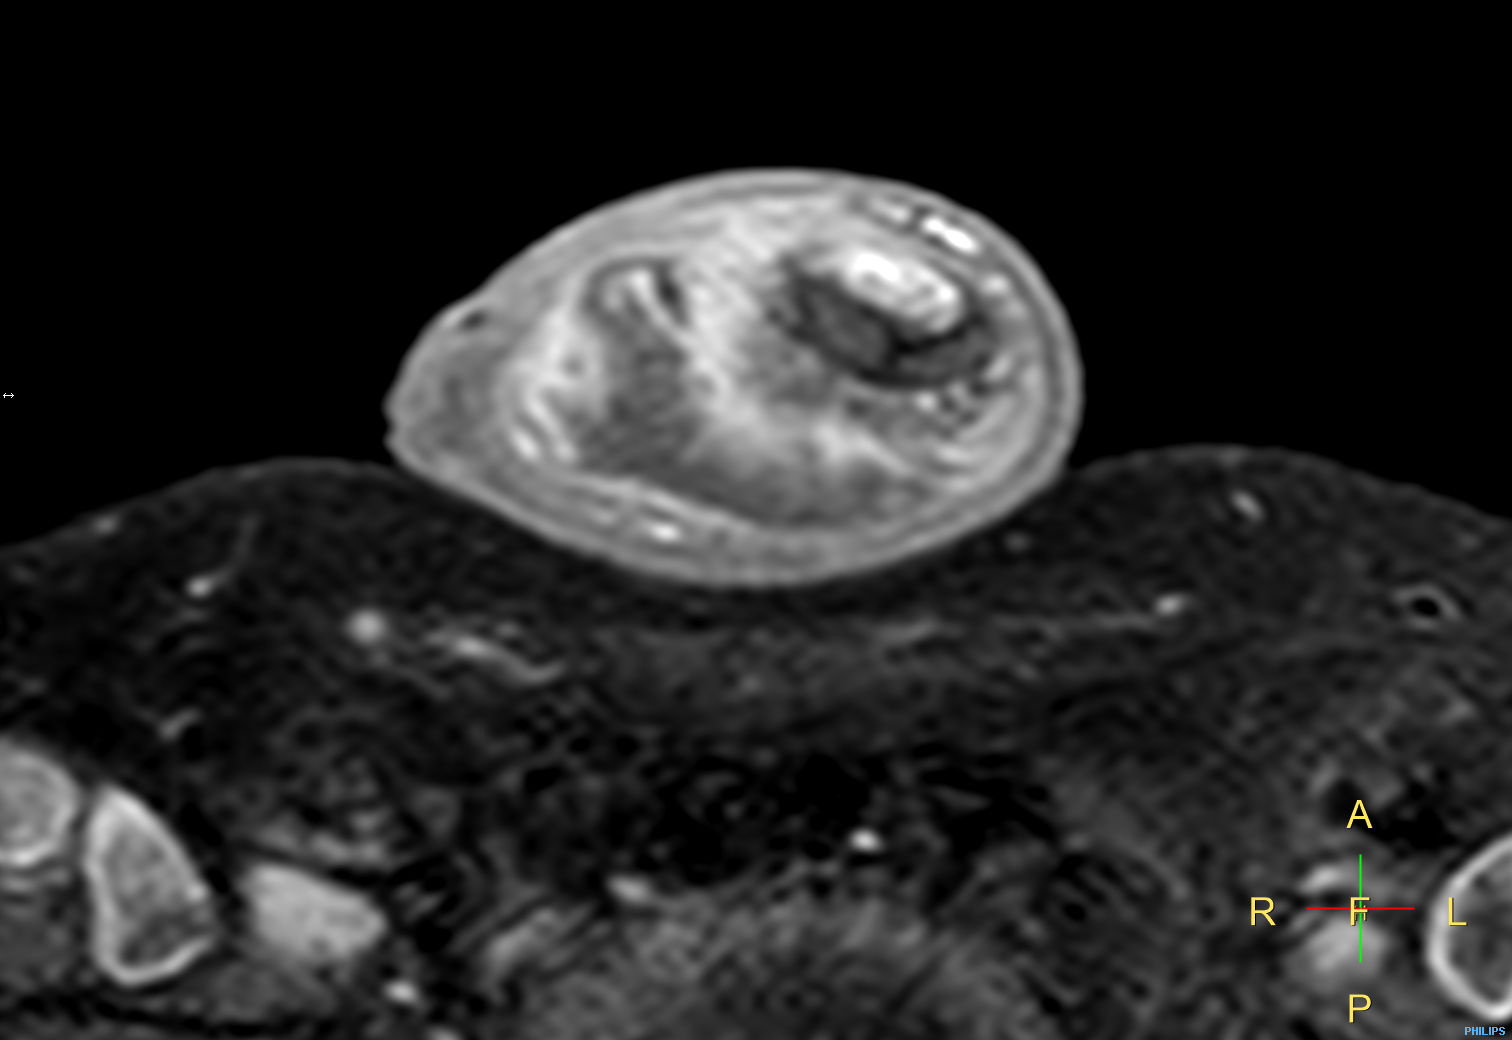

Patient with a penile carcinoma. ExamCard includes Compressed SENSE to shorten exam time, diffusion to achieve high contrast between background and lesions, and MultiVane XD for motion-free imaging in short scan time.

T2w TSE Compressed SENSE